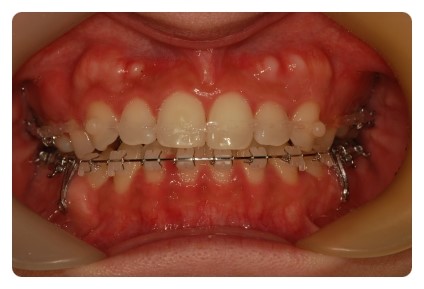

이번에는 새로운 장치가 또 추가되었어요

상악틈 줄이기 위한건데 앞니에도 고무줄을 뙇 !! 고무줄이 자꾸 미끄러져 올라가서 동그란것도 하나 붙이고

가족들이 밥풀끼인줄 알았다고 ;;